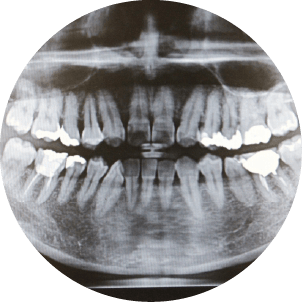

5. 05レントゲンの画像

レントゲン撮影

必要に応じて、レントゲンを撮影し、歯を支える骨の状態を確認します。骨の吸収(骨の減少)が見られる場合、歯周病が進行していることが分かります。